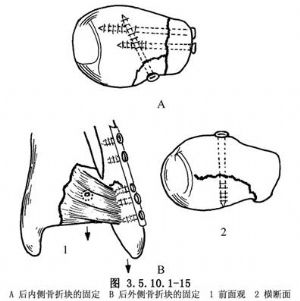

12.7 7.後踝骨折內固定術(Internal Fixation for Fracture of Posterior Malleolus)

後踝指脛骨後緣。在嚴重骨折時,常出現後下脛腓韌帶附於脛骨後外側一大塊骨片連同其附着韌帶斷裂,形成後踝撕脫骨折。

(1)內踝骨折合併後內骨折塊少見。如出現,常位於內踝骨折片之後,可經後內方入路顯露。復位後用螺釘固定。

(2)如後踝連同外踝一併骨折,整復外踝後,可使後外側骨塊一同復位,因爲兩骨塊都附着有後聯合韌帶。小的撕脫骨折片或骨塊在矢狀面<1/5關節面時,不必復位與內固定。大的骨塊則必須小心整復,消除關節面的臺階。然後經後內側顯露、整復,螺釘固定。如由前內側向後插入拉力螺釘,則需在踝關節前上方另做小切口(圖3.5.10.1-15)。